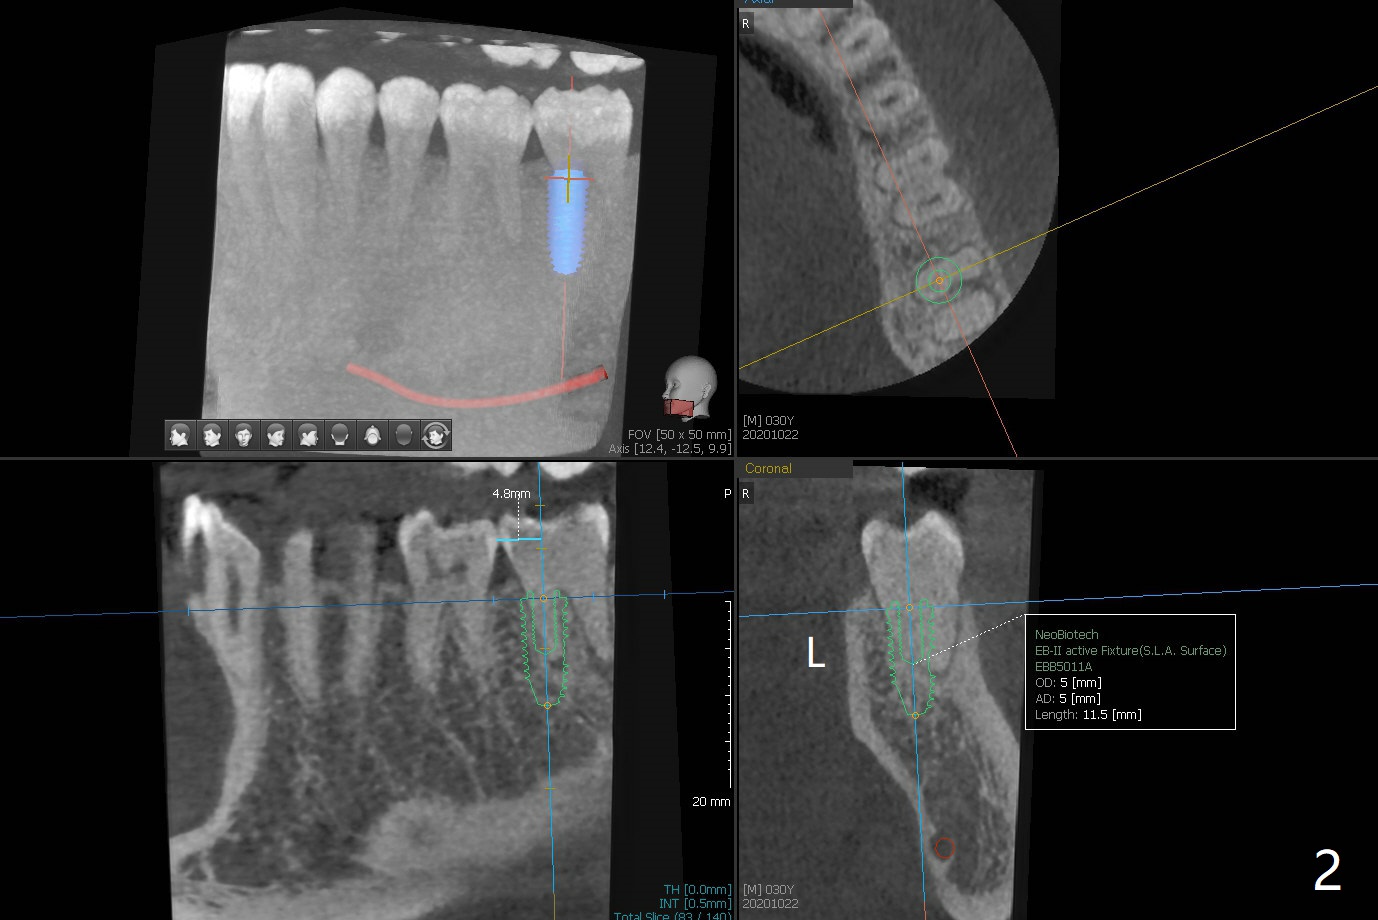

30岁男小的时候双侧下颌第二磨牙埋伏,拔除智齿后,前者经过矫正才萌出。近几年两个第二磨牙都出现疼痛,牙髓病专家认为左侧预后不佳(图一),需要拔除种植(图二)。注意去除根尖肉芽组织。左下7治疗完成后病人要求右下7拔除植牙(图三,四)。